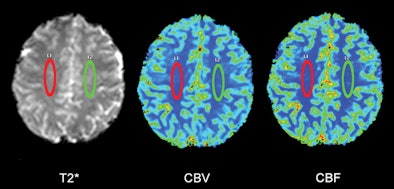

| Regions of interest (ROI) were placed in the white matter of a 38-year-old healthy subject at the level of the semioval centers to avoid arterial and venous structures. ROIs were in the same position and same measurements in all patients with MS and all control subjects. T2* = T2*-weighted MRI; CBV = cerebral blood volume; CBF = cerebral blood flow. Images courtesy of Radiology. |

The researchers used contrast-enhanced MRI to assess blood flow in the brains of both groups. MRI exams were conducted on a 3-tesla scanner (Achieva, Philips Healthcare) with an eight-channel phased-array head coil.